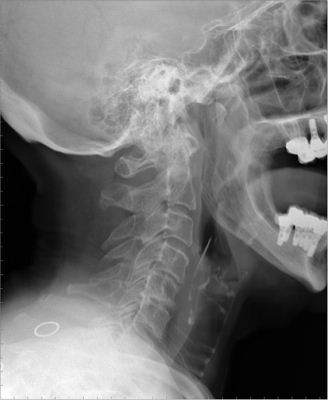

JFC Carcinoma adenoide quístico.